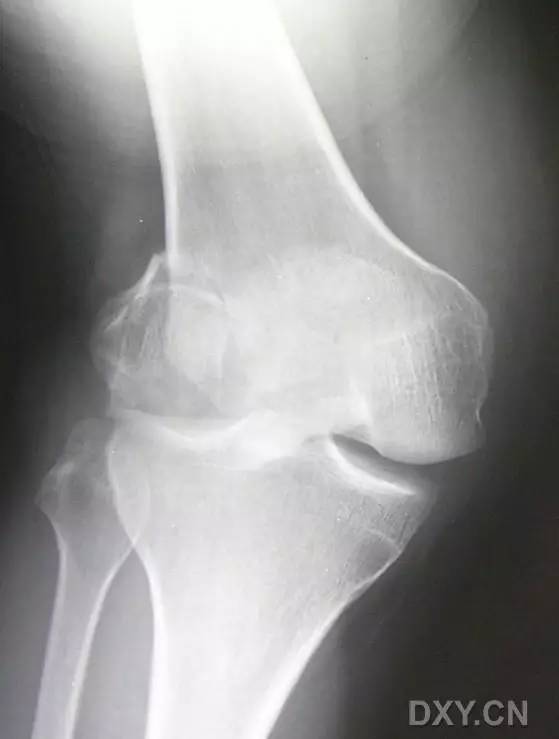

9. Pellegrini-Stieda 损伤

膝关节内侧副韧带附着处的内侧股骨髁的撕脱性骨折。

(来源:radiopaedia)

11. Bumper 骨折(保险杆骨折)

是汽车保险杠撞击膝关节外侧,导致的胫骨平台粉碎性骨折,伴有软骨面挫裂和腓骨头骨折。初诊,X 线上正侧位很容易忽略平台的粉碎性,CT 平扫及重建可明确伤情,MRI 可了解副韧带及叉韧带情况。